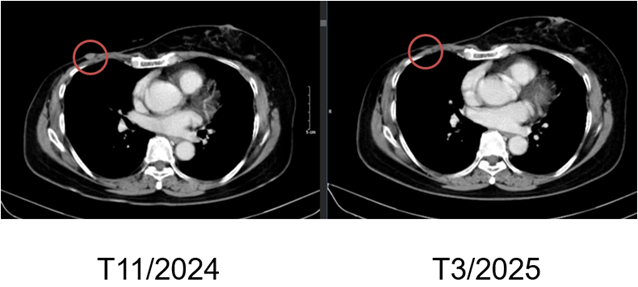

Hình 7. Hình ảnh chụp CT ngực trước và sau điều trị: Tổn thương tái phát thành ngực

– Chụp cắt lớp vi tính ngực:

+ Thành ngực phải có nốt đặc đường kính 5mm – theo dõi tổn thương tái phát

Hình 4. Hình ảnh chụp CT ngực sau điều trị: Tổn thương tái phát thành ngực